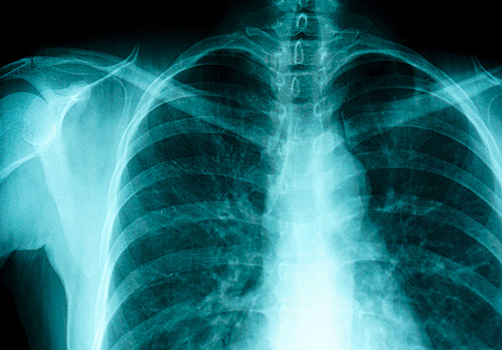

Что такое остеопороз Это болезнь, при которой из костей уходит часть кальция, и они становятся хрупкими. Из-за остеопороза увеличивается риск переломов. Всем известно, что чаще всего это происходит с возрастом — у женщин в менопаузе и постменопаузе. Но на самом деле группа риска гораздо шире. К уменьшению плотности костей в молодом возрасте (в том числе у мужчин) могут привести: Вредные привычки (курение, алкоголизм), Недостаток кальция и витамина D, Ревматоидный артрит, Сахарный диабет 2-го типа, Глюкокортикоидные препараты, Гормональные контрацептивы, Заболевания щитовидной и половых желез. Вот почему женщины старше 45 лет, а также все, кто имеет хотя бы один из перечисленных факторов риска, должны регулярно проходить профилактическое обследование — денситометрию. Денситометрия — самый точный и один из самых безопасных методов диагностики остеопороза на сегодняшний день. Существует несколько видов денситометрии. Ультразвуковая денситометрия Как видно из названия, исследование проводится с помощью ультразвука. Оно абсолютно безопасно, а потому разрешено даже беременным и кормящим женщинам. Но качество информации довольно низкое. КТ-денситометрия Обеспечивает высокое качество информации, но лучевая нагрузка довольно высока, а потому метод противопоказан при беременности. Двухэнергетическая рентгеновская денситометрия Это очень высокая точность, низкий уровень облучения и быстрое получение результатов — аппарат не просто измеряет плотность костей, но сразу же соотносит их с нормой и выдает величину отклонения. Обычно во время денситометрии исследуется не все тело целиком, а только отдельные участки, наиболее подверженные переломам (поясничный отдел позвоночника и шейка бедра). И дело не только и не столько в том, что такая избирательность сокращает время процедуры и позволяет снизить лучевую нагрузку. На самых ранних стадиях заболевания признаки остеопороза выявляются в поясничных позвонках L2-L4, а по статистике, переломы при остеопорозе чаще возникают в шейках бедренных костей. Это и есть оптимальные точки для сканирования. Остеопороз вполне излечим. Лечение медикаментозное. При нарушениях эндокринной системы выписываются лекарства, способствующие восстановлению гормонального фона. При недостатке кальция советуют принимать витамин D. В общем, суть лечения состоит в том, чтобы остановить процесс вымывания кальция из костей и запустить процессы восстановления костной ткани. Поэтому принципиально важно обнаружить болезнь до того, как разрушение костей станет почти необратимым. Вот для этого и применяют метод денситометрии. Фото: Shutterstock